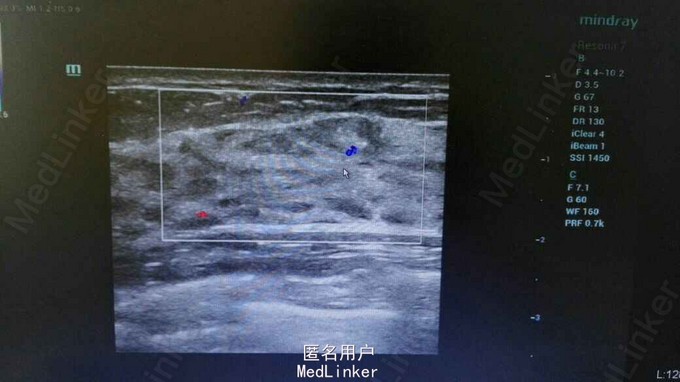

女性,25岁,发现右乳肿物2周。2周前无意中发现右乳肿物,不规则状,约3*2.5cm,无疼痛,无红肿,无乳头溢乳,与月经周期无明显相关。既往体健。

右乳9点钟方向,距离乳头5cm可扪及一肿物,不规则状,约3*2.5cm,质中,边界欠清,按压有轻微疼痛,活动度一般,挤压双侧乳头无液体流出。双侧腋窝LP(—)。我院乳腺彩超示:右乳实性肿物,BI—RADS—3类,(乳腺纤维瘤?)。